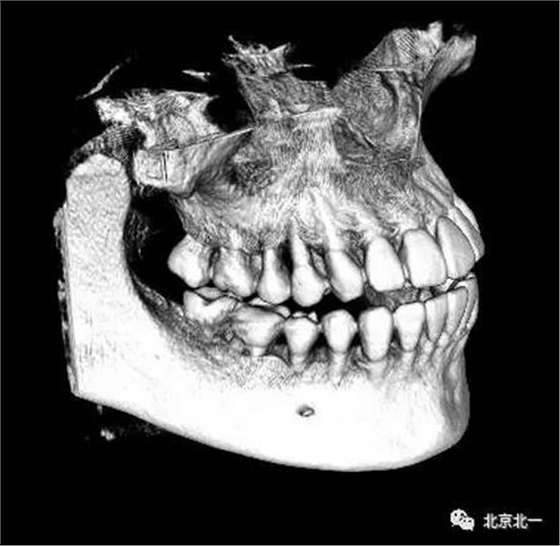

圖四:三維重建

圖五:三維重建可見(jiàn)牙冠突破舌側(cè)

圖九:重建后可見(jiàn)牙冠位于第二磨牙遠(yuǎn)中,舌側(cè)傾斜。